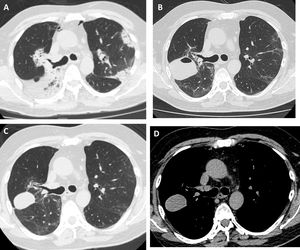

Tomografía de tórax de alta resolución. A) Antes de realizar CBTB: consolidaciones bilaterales con broncograma aéreo de distribución periférica y peribroncovascular. B) Un mes posterior a CBTB: lesión con nivel hidroaéreo en el lóbulo superior derecho. C y D) Tres meses posterior a CBTB: disminución de tamaño de la lesión con desaparición o reabsorción del contenido aéreo y persistencia del contenido hemático (hematocele).

Se trata de un varón no fumador, sin antecedentes de relevancia, de 55 años que fue derivado a nuestra institución por una neumonía de lenta resolución. Un mes antes presentó tos, disnea y opacidades pulmonares bilaterales. Recibió tratamiento antibiótico empírico con amoxicilina-sulbactam y claritromicina, luego piperacilina-tazobactam y finalmente vancomicina, sin mejoría clínica y con empeoramiento de la oxigenación. Al ingreso se encontraba hipoxémico, con una saturación de oxígeno del 90% respirando aire ambiente. La analítica no arrojó resultados relevantes: recuento de eosinófilos dentro de límites normales, velocidad de eritrosedimentación de 34mm en la primera hora, serología para el VIH negativa, ANCA, FAN negativos y CPK dentro de los límites normales. La tomografía computarizada (TC) de tórax evidenció consolidaciones bilaterales, a predominio periférico, con distribución peribroncovascular y algunas zonas con signo de halo invertido (fig. 1A). Realizamos una broncoscopia con lavado broncoalveolar (LBA) y toma de biopsia transbronquial por criosonda de 1,9mm. Se tomaron 5 biopsias en el lóbulo superior derecho, tres en el segmento posterior y dos en el segmento apical. El procedimiento concluyó sin complicaciones. La anatomía patológica arrojó hallazgos característicos de neumonía en organización. Comenzamos tratamiento con prednisona en dosis de 0,5mg/kg/día. El paciente evolucionó sin fiebre y con mejoría progresiva de la disnea. Al mes de tratamiento en una radiografía de tórax de control se evidenció una cavidad en el campo superior del hemitórax derecho. Para caracterizar la imagen se realizó una TC de tórax sin contraste que mostró una formación de bordes lisos, de 3cm de diámetro en el segmento posterior del lóbulo superior derecho (fig. 1B). A pesar de encontrarse asintomático, con una analítica normal y velocidad de eritrosedimentación de 5mm en la primera hora, tomamos un LBA al segmento pulmonar afectado. Los resultados microbiológicos fueron negativos y la celularidad del LBA normal. Se interpretó que la imagen era secundaria a un neumatocele con contenido en su interior producto de la CBTB. Decidimos optar por una conducta expectante y seguimiento clínico. A los dos meses el paciente se encontraba asintomático y la TC mostró la persistencia de la cavidad con una densidad homogénea de 30-40 unidades Hounsfield, en contacto con la pleura y la cisura mayor (fig. 1C y D).